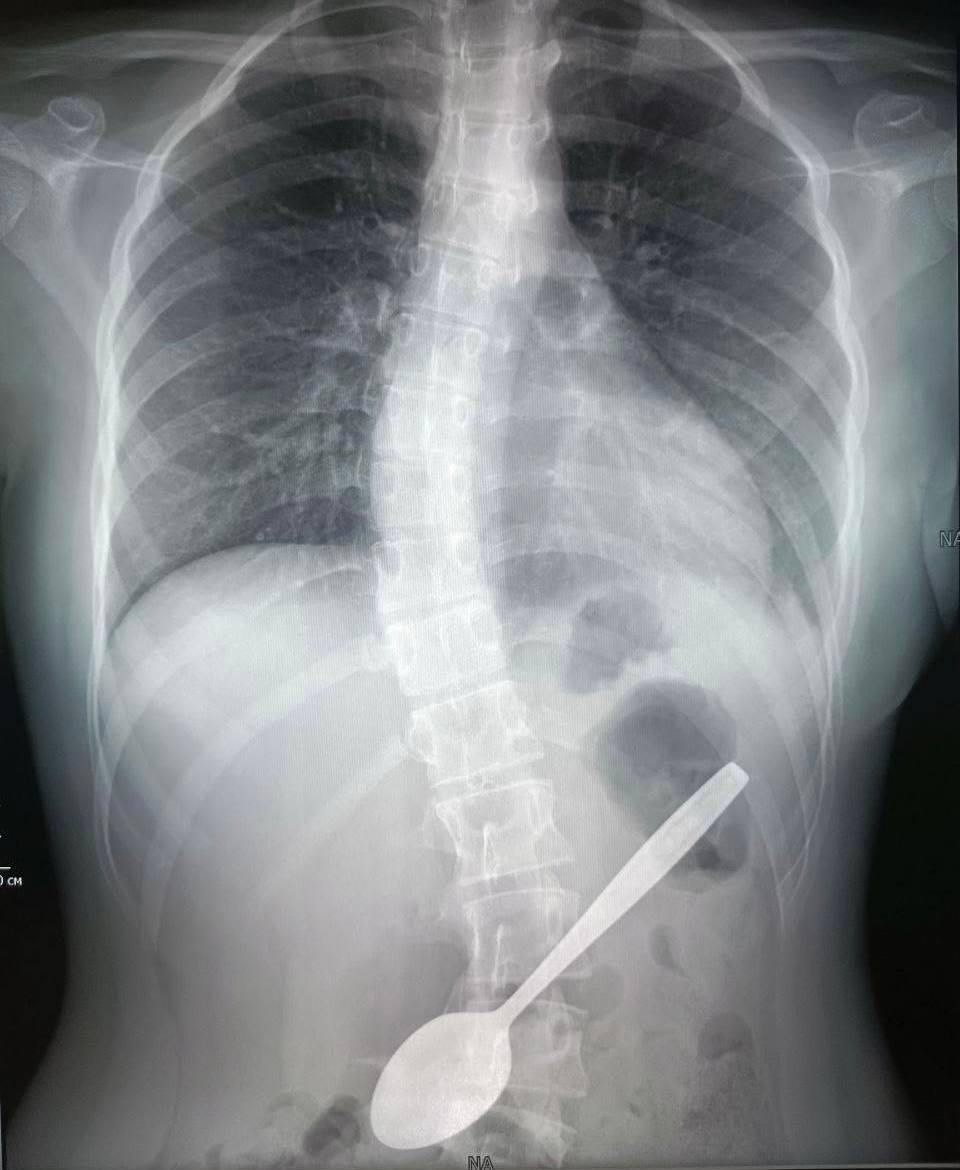

Врачи Центра Рошаля извлекли 15-сантиметровую ложку из желудка девочки

Девочке сделали рентген и эндоскопически извлекли столовый прибор.